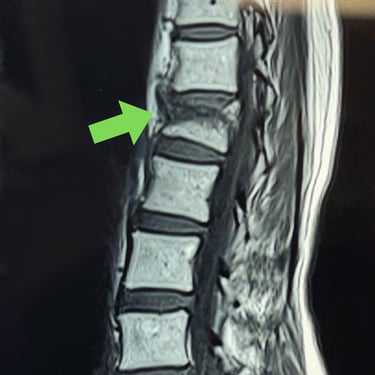

Fractura vertebral lumbar – Artrodesis con tornillos transpediculares (FTP).

La fractura vertebral lumbar es una lesión que puede comprometer la estabilidad de la columna y generar dolor, deformidad o déficit neurológico. En casos seleccionados, el tratamiento quirúrgico mediante artrodesis con tornillos transpediculares (FTP) permite una fijación firme de las vértebras afectadas, restaurando la alineación y brindando estabilidad inmediata. Esta técnica reduce el dolor, previene el desplazamiento vertebral y protege las estructuras neurológicas. La intervención oportuna, junto a una adecuada rehabilitación, favorece una recuperación funcional segura y mejora significativamente la calidad de vida del paciente.